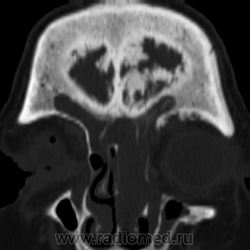

Полипозный процесс в пазухах? А по поводу самой кости - либо эндокринные дела, либо (менее вероятно) фиброзная дисплазия.

По пазухам полипоз как минимум, а вот с костью... Не получилось бы так, что какое-то образование вызывает такой реактивный процесс? Дисплазия вряд ли... не похоже. Эндокринное и так локально изменена кость?

Возможно реакция кости на хроническое воспаление в пазухах. На саркому не похоже.

Согласен, такие же мысли. Но такой "махровой" реакции ни разу не видел... Но то, что с двух сторон (оба кортикала) изменения - это, вероятнее, рекция на то, что в пазухе. А раз такие выраженные изменения, то, вероятно, процессу много лет. Итого - полипоз с периодическими обострения хронического синусита?

Значит так, Сергей Николаевич, представьте исследование корректно: с полной клиникой, рентгенограммами, подробной серией КТ. Пока это "рак, сифилис и несчастная любовь". Есть мягкотканная масса в пазухах и полости носа, есть ли деструкция стенок - по этим сканам судить нельзя. Есть спикулообразный периостоз в лобной кости, который м.б. при десятке заболеваний: от серповидноклеточной анемиии до остеосаркомы или мтс. Есть ли связь между этими изменениями - по тому, что вы показали - не видно.

Диагноз при поступлении: обострение полипозного-гнойного хронического синусита, реактивный отек века. Сейчас будет видео.

Посмотрела видио и еще больше утверждаюсь в мысли, что это реакция костных стенок пазух на длительно текущий воспалительный процесс в пазухах.

1. Считаю, в первую очередь, необходимо сделать биопсию образования в полости носа. Возможно, результат все объяснит (напр. лимфома)

2. Есть два различных заболевания, при этом, в лобной кости не исключена фиброзная дисплазия, болезнь Педжета.